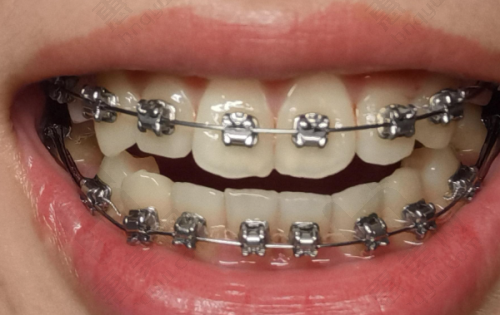

牙齿矫正项目也特别出色,能做全同步带状弓矫正、时代天使隐形矫正、儿牙时代天使早期矫正等项目,大人小孩都可以同时来进行矫正。除此之外,还有全瓷牙冠、牙齿瓷贴面、洗牙、补牙、儿童牙齿涂氟、牙周护理(超声洁牙 + 抛光套餐98元,清除茶渍烟渍)、残根接续、烤瓷牙、根管治疗、牙齿美白、地包天治疗、活动义齿等其他项目。

| 传统托槽矫正 | 8000元起 |

| 金属矫正 | 6000元起 |